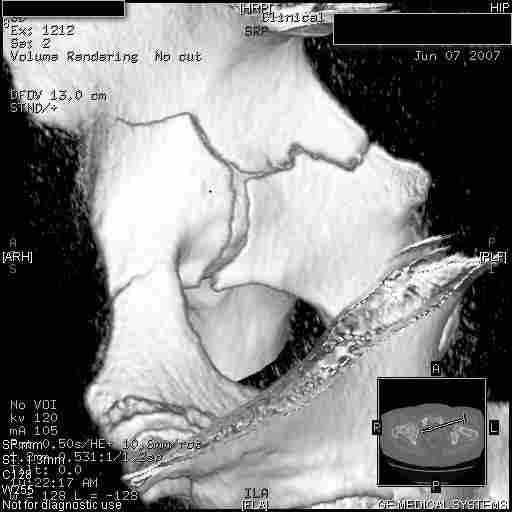

Удалось сегодня вывести пациентку в соседнюю больницу, где есть кт. Срезы сделаны только горизонтальные.

Следом 3d